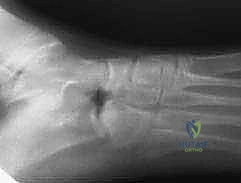

Thorough preoperative planning is non-negotiable. Standard radiographic evaluation includes a weight-bearing anteroposterior pelvis, a false profile view of Lequesne and de Sèze to assess anterior coverage, and a Dunn or cross-table lateral view to evaluate for concurrent cam morphology. The von Rosen view (abduction and internal rotation) is critical to confirm that the femoral head can be concentrically reduced into the dysplastic acetabulum once reoriented.

Computed tomography with three-dimensional surface rendering is heavily utilized to map the precise osseous anatomy, evaluate acetabular version, and plan the osteotomy trajectories. Magnetic resonance imaging or MR arthrography is indicated to evaluate the integrity of the acetabular labrum and articular cartilage. Concomitant labral tears are common and may be addressed via hip arthroscopy either prior to or simultaneously with the periacetabular osteotomy.